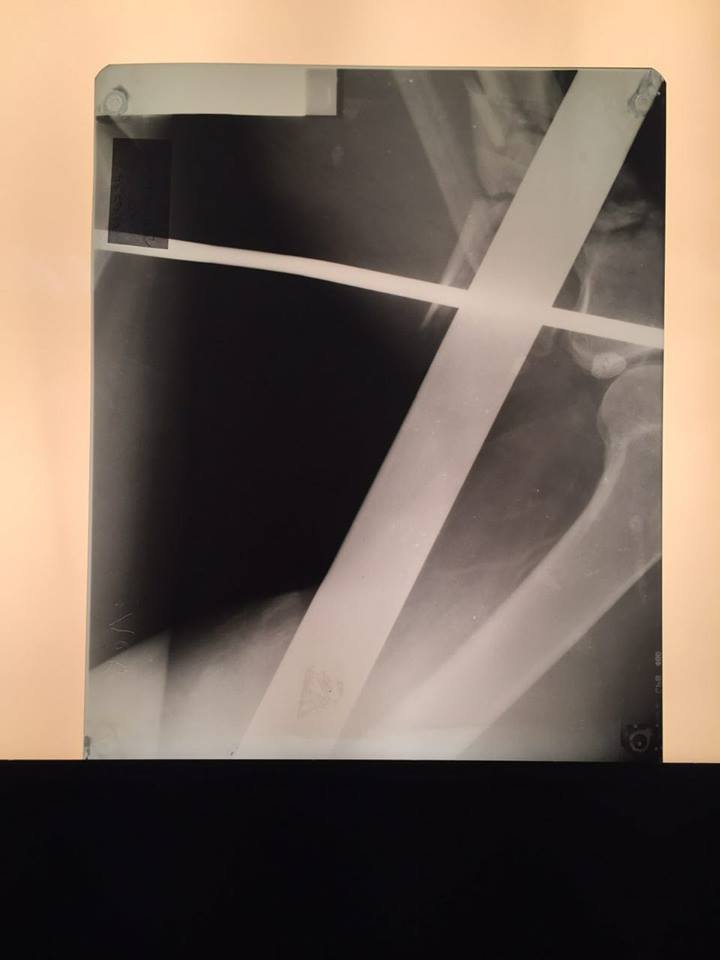

Заведующий приемно-диагностического отделения больницы имени Мечникова Петр Давыденко рассказал, что металлический профиль буквально насквозь проткнул мужчину.

"Итог: инородное тело левой голени, левого бедра, левой половины таза, левой половины поясничной области, открытый многооскольчатый перелом верхней трети левой большеберцовой кости, травматический шок", - отметил врач.

Первую медицинскую помощь пострадавшему оказали в Царичанке, после чего мужчину доставили в Мечникова. Осмотр немедленно провели дежурные травматологи, урологи, хирурги и нейрохирурги. Провели операцию по удалению инородного тела, ПХО ран, лапароцентез, а также объемное переливание препаратов крови.